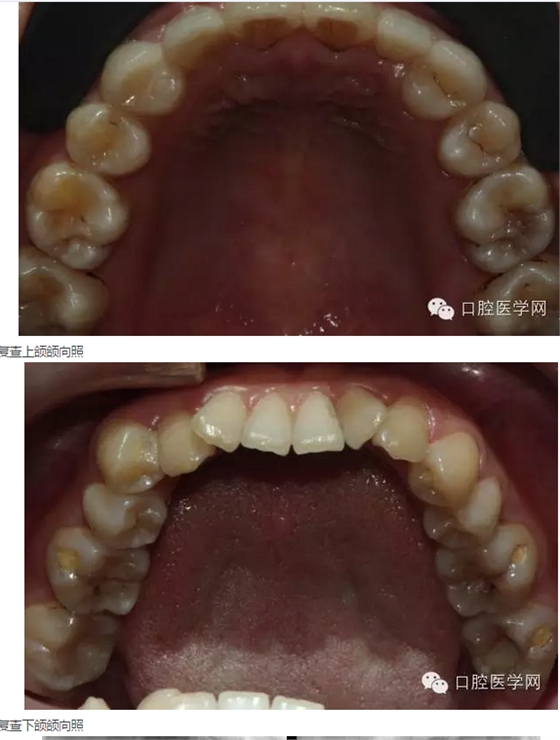

來源于口腔醫(yī)學(xué)網(wǎng)